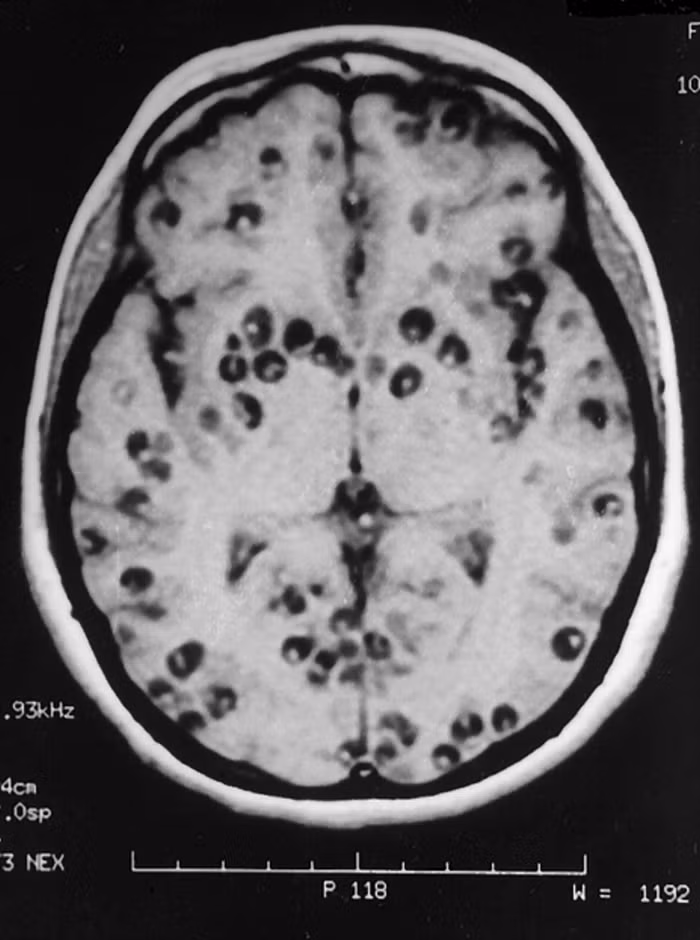

Tiến sĩ Praveen Gupta - Trưởng khoa thần kinh tại Bệnh viện Fortis ở Gurga (Ấn Độ) cho biết: “Qua phim chụp, chúng tôi phát hiện não bé gái có 100 trứng sán dây. Cô bé đã vô tình ăn thức ăn bị nhiễm sán dây. Bé liên tục bị đau đầu dữ dội, co giật và động kinh trong 6 tháng qua. Khi nhập viện, cô bé gần như bất tỉnh do u nang và não bị sưng lên”.

Các bác sĩ đã chẩn đoán cô bé bị nhiễm ấu trùng sán lợn hệ thần kinh trung ương. Đây là bệnh ký sinh trùng phổ biến nhất của hệ thần kinh và là nguyên nhân chính gây bệnh động kinh ở các nước đang phát triển.